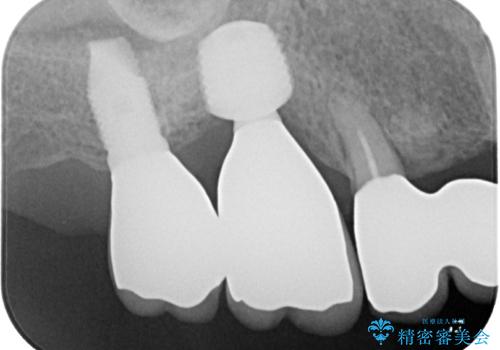

- インプラントが脱落してしまったとのことで来院された患者様です。

歯肉は綺麗に治癒しており、インプラント埋入に十分な骨があったため、速やかにインプラント埋入を行うこととしました。

インプラント埋入の状態が良ければ即日で仮歯を装着し、十分な生着が確認され次第、オールセラミッククラウンにて補綴治療を行うこととしました。